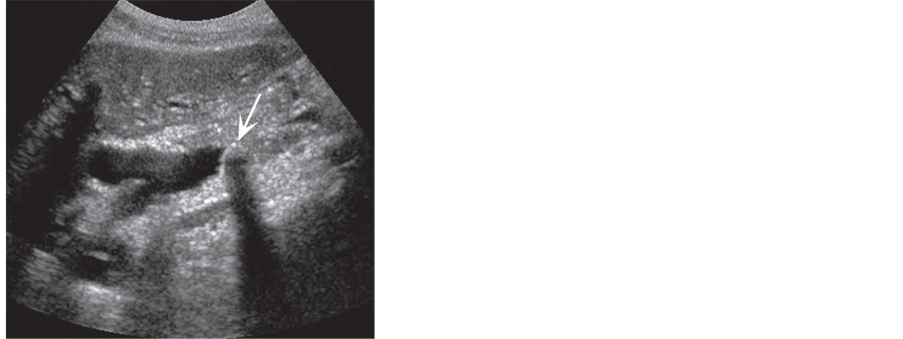

The classic appearance of CBDS is a rounded echogenic lesion with posterior acoustic shadowing [47] . Although TAUS is considered the gold standard for detecting cholelithiasis [48] having a sensitivity of approximately 99% and a specificity of 99% for detection of GB stone [49] , but sensitivity of TAUS in diagnosis CBDS varies from 20% to 80% depending on the operator [27] [38] , due to the following causes:

1) Some time no fluid rim will be seen around an impacted distal CBDS because it is compressed against the duct wall. The lateral margins of the stone are therefore not seen, decreasing the conspicuity of the stone, versus a stone seen in the gallbladder or proximal duct, where it is likely to be surrounded by bile [38] (Figure 3(b)).

2) Small stones may lack good acoustic shadows and appear only as a reproducible

bright, linear echogenicity, either straight or curved. Awareness of this subtle appearanceof CBDS definitely improves their detection [47] (Figure 3(a)).

4) CBDS often do not show acoustic shadowing [50] , possible reflection and retraction of the sound beam of the duct wall and the location of the duct beyond the optimal foci of the transducer [51] (Figure 3(a)).

Figure 3. Common bile duct stones. (a) Small stone (arrow) may not show shadowing; (b) Large stone (arrow) has classic findings within a dilated CBD [24] .